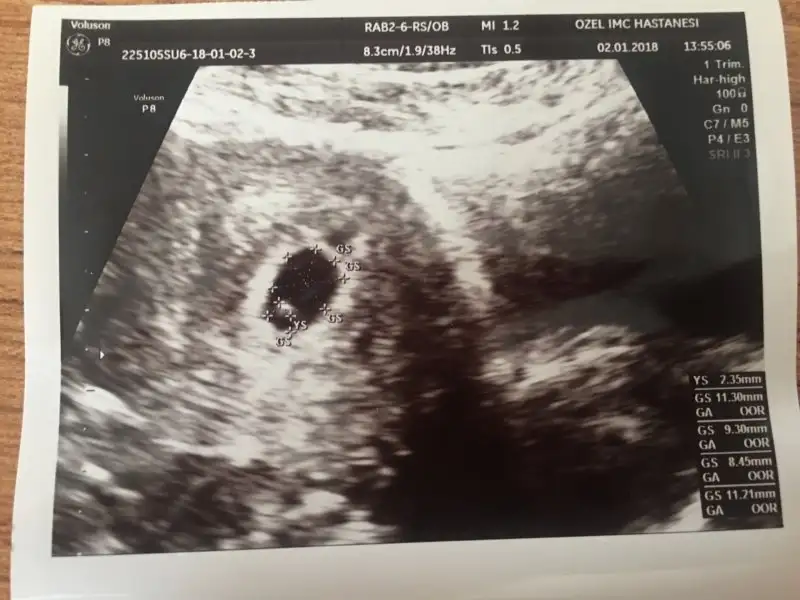

Canimm tesekkur ederim:) insallah sende duyarsin kalp atislarini minik kusunun:) birazdan ultrason resmini de atcam size gelsin tahminler:) :)